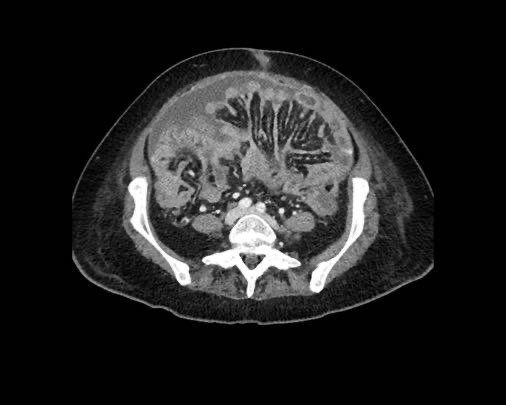

Hình ảnh

Hình ảnh CT của một bệnh nhân ung thư phúc mạc.

Một lượng nhỏ dịch cổ trướng hiện diện ở góc phần tư trước bên phải.

Các đường dày dạng nốt vuông góc với thành ruột được ghi nhận.

Hình ảnh này đại diện cho tổn thương xâm lấn mạc treo ruột lan rộng (mũi tên).